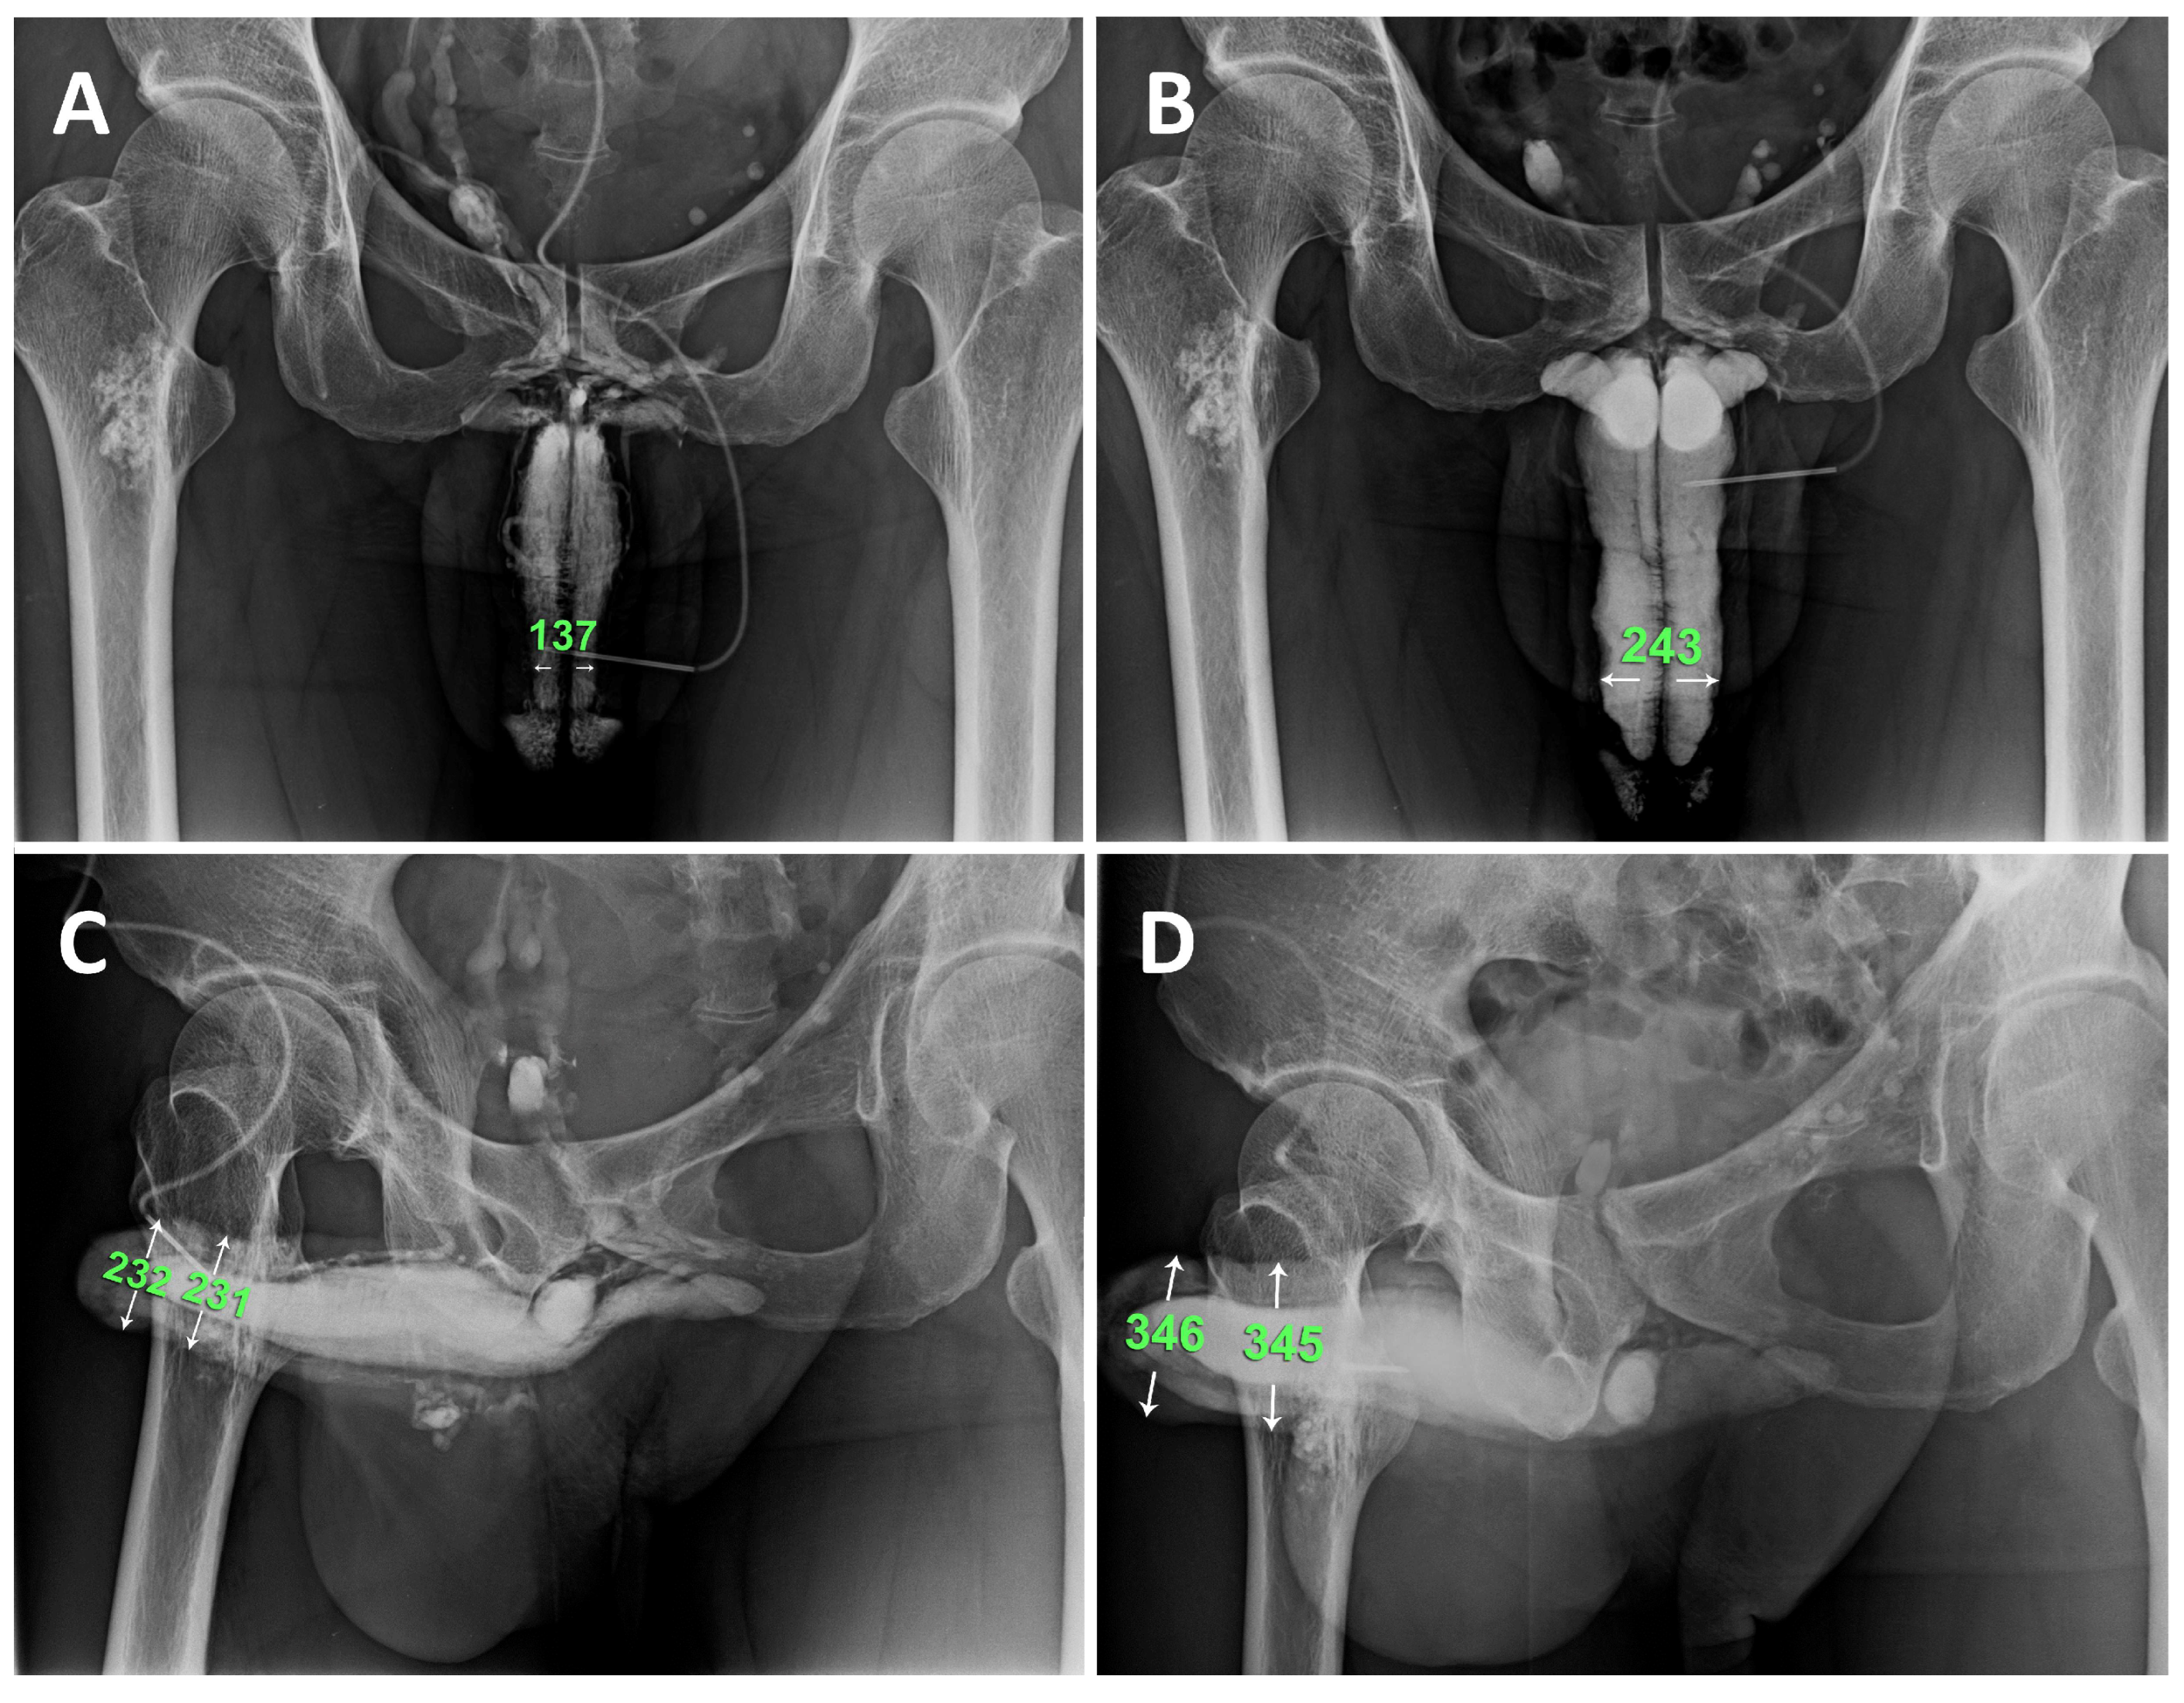

Figure 5.

Representative example is a patient who undergoing combined surgery strategy. A) Preoperative anterior-posterior view of the pilot cavernosogram showing the intracavernous contract medium draining back to the periprostatic plexus, internal pudendal, and internal iliac veins immediately. The radiopacity of the penile crura is just equivalent to that of the femoral cortex, and the diameter of the corpora cavernosa (CC) is 13.7 mm. B) Six months postoperatively, a parallel cavernosogram shows the marked enhancement of intracorporeal retention and radiopacity between the penile crura and the femoral cortex. At the same time, the diameter escalates to 24.3 mm. C) A 30-degree oblique view of the pilot cavernosogram showing the intracavernous contract medium draining back to the periprostatic plexus, internal pudendal, and internal iliac veins immediately. The radiopacity of the penile crura is just equivalent to that of the femoral cortex. Meanwhile, the diameter of the glans penis and penile shaft is 23.2 mm and 23.1 mm, respectively. D) Six months postoperatively, a parallel cavernosogram shows the marked enhancement of intracorporeal retention, radiopacity between the penile crura and that of the femoral cortex, and conspicuously significant penile girth augmentation. Additionally, the diameter of the glans penis and penile shaft escalated to 34.6 mm and 34.5 mm, respectively.

Figure 4). However, the girth enhancement was evident after six months postoperatively (

Figure 5). Although the satisfaction rate was only 81.3% (13/16), intracorporeal retention and improved erection quality were unexceptional in the AVW group. Two patients reported poor sleep patterns resulting from painful nocturnal penile erections postoperatively, which lasted for three weeks. One patient in the SF group presented with a self-limited infection, which was treated with oral antibiotics.

26]. One intriguing aspect is the potential for hypertrophy in the smooth muscle fibers of the corpus cavernosum (CC) sinusoidal wall, akin to the hypertrophy observed in uterine smooth muscle during pregnancy. In this study, the CC smooth muscle fibers can be hypertrophied as CC diameter is apparent enlargement in those cavernosograms after six months postoperatively (

Figure 5) but not in the immediate postoperative ones (